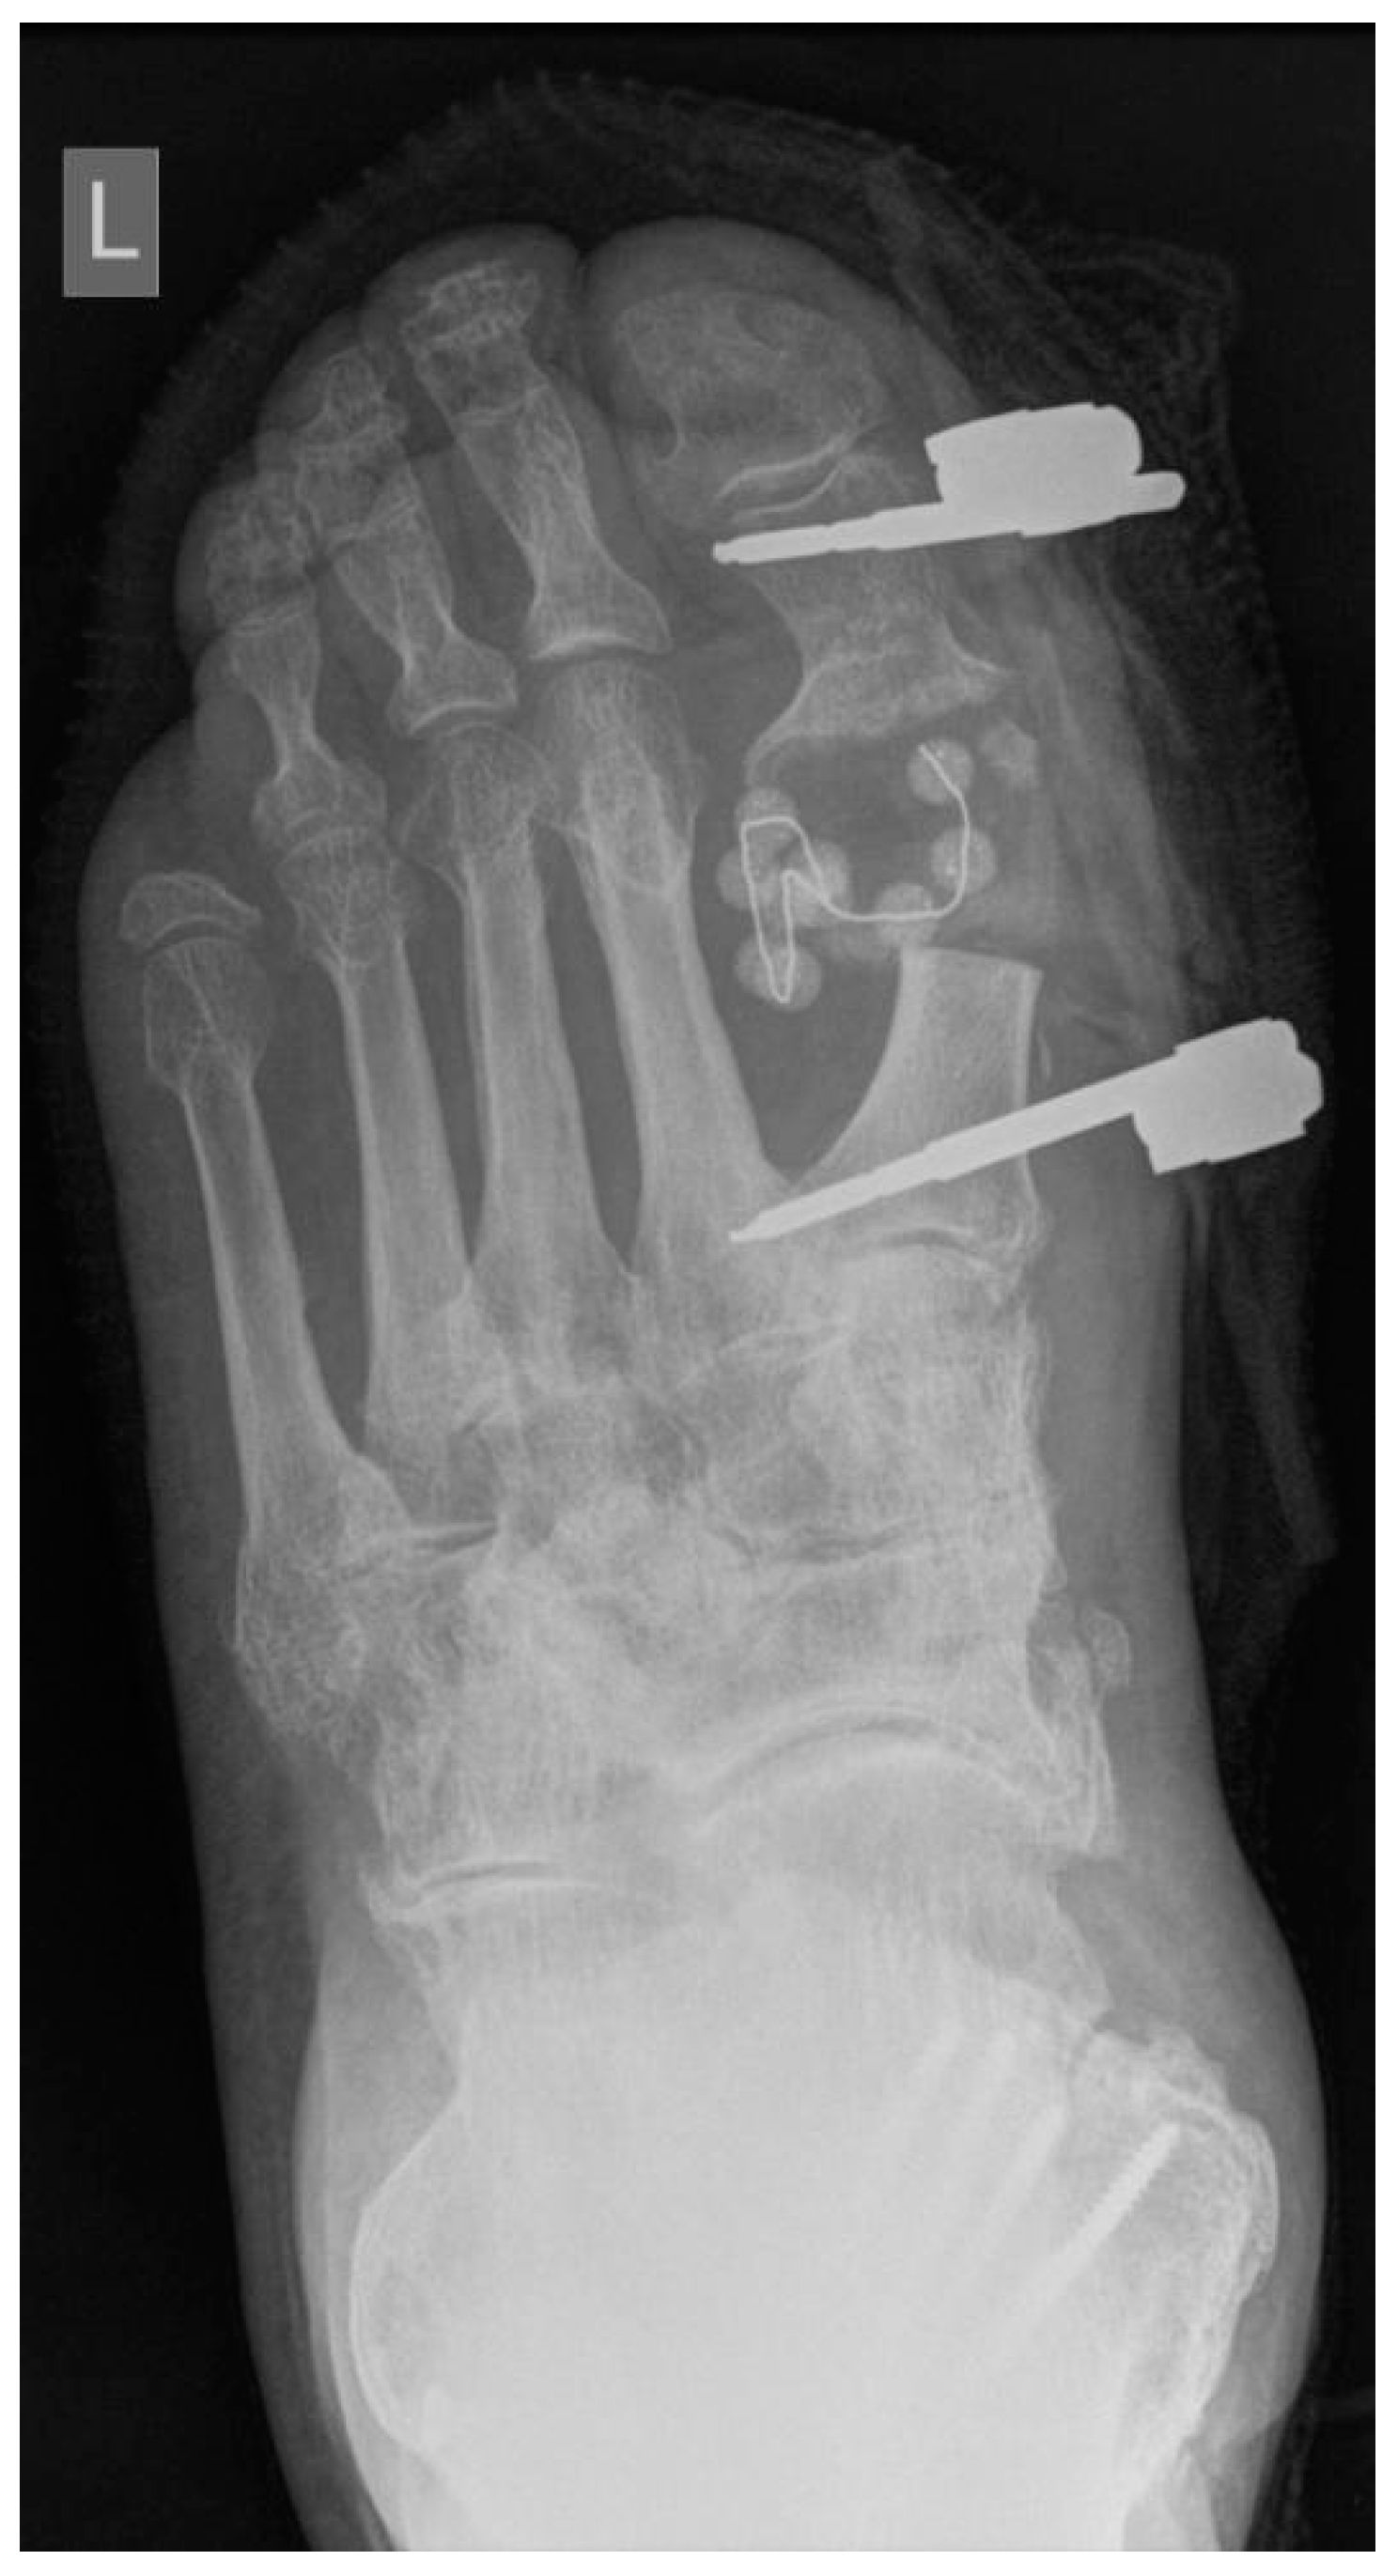

2.3. Surgical Technique